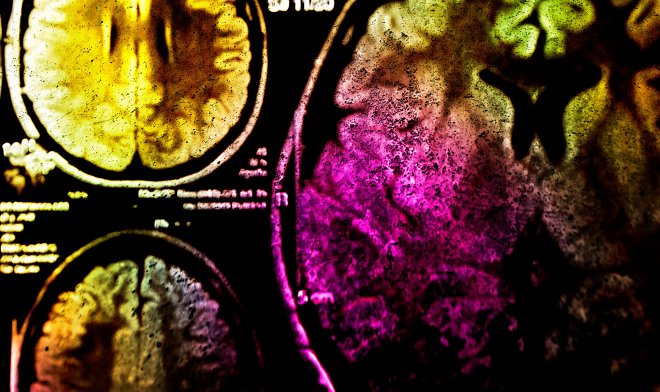

Исследователи из Института исследования рака в Лондоне разработали новый метод борьбы с раковыми клетками, получивший название «фотоиммунотерапии». Она основана на технологии флуоресцентной хирургии, при которой синтетическая молекула-маркер связывается с белками в раковых опухолях. Если затем осветить ткани, молекула начинает излучать свет и тем самым упрощает поиск и удаление раковых клеток.

Британские ученые модифицировали базовую молекулу для флуоресцентной хирургии, добавив в нее активный компонент. При облучении инфракрасным светом он начинает генерировать активную форму кислорода, которая уничтожает живые клетки. На первом этапе флуоресценция помогает выявить раковые клетки и удалить их хирургическим путем. На втором врач освещает обработанный участок инфракрасным светом и кислородная атака уничтожает пропущенные единичные клетки, полностью удаляя все следы рака.

Для того чтобы не пострадали остальные живые ткани, синтетическую молекулу привязали к белку EGFR, основному элементу глиобластомы рака мозга. При проведении опытов на грызунах раковые клетки полностью погибали уже через час после воздействия инфракрасного излучения. Кроме того, такое вмешательство активировало иммунную систему, которая помогала справиться с остатками раковых клеток, поэтому технология и получила название «фотоиммунотерапия».